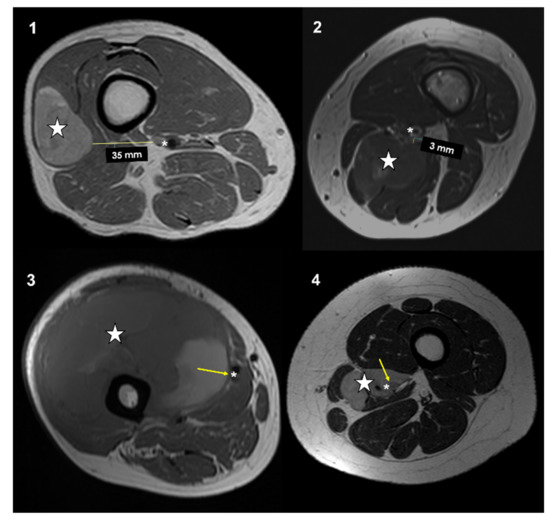

All patients had an MRI performed within a maximum of 21 days prior to surgery. All MRI were performed with a high field (1.5 Tesla or higher) and with the standard sequences, which included T1w, T2w, STIR, or T2 fat sat. Magnetic resonance imagines were retrospectively reviewed on a PACS (Carestream Vue PACS v. 11.4.1.1102) by two expert oncologic radiologists (PS and FP). Imaging analyses were performed in consensus. The closeness to major vessels was defined as the minimum distance between the tumor and the main vascular bundle. This distance was measured on the axial slices of preoperative T1-weighted MRI [19]. Distance between the major vascular bundle and the tumor was classified into four types according to Fujiwara et al. [15]: type 1, >5 mm; type 2, ≤5 mm and >0 mm; type 3, attached to the tumor; type 4, surrounded by the tumor (Figure 1).

Figure 1. Types of vascular proximity based on MRI T1w axial images performed in four different patients affected by soft-tissue sarcomas of the thigh and popliteal fossa: type 1: >5 mm; type 2: >0 mm and <5 mm; type 3: in contact; type 4: surrounded. Stars (neoplasms), asterisks (main vessels), arrows (tumor-vascular contact).